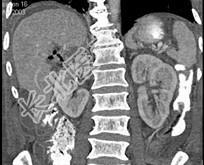

- 单项选择题男,44岁, 发热、右上腹痛半月,加重1天, 查体:右下肺呼吸音低, 影像检查如图,最佳诊断是 ( )

A、腹腔积液

B、膈下脓肿

C、肝包膜下出血

D、肝硬化腹水

E、肝癌